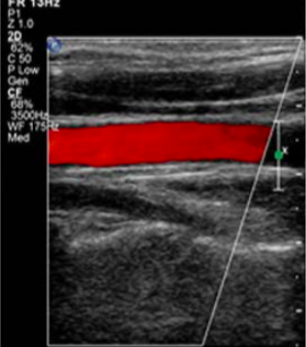

In which direction is this image steered?

to the left

steering color doppler imaging to left → diagonal border points to 6-9 o’clock region